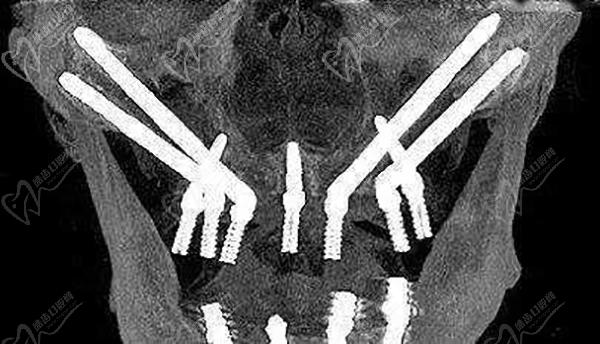

上海鼎植口腔以疑難種植為特色,專研“缺骨難種之牙”。鼎植集團的“VIIV專li缺骨種牙”技術(shù)為患者帶來全新的種牙體驗。即使面對牙骨量缺失重度的患者,也可以立即種牙,避免了痛苦、漫長的植骨,而是采取人體的天然骨頭(顴骨或翼板區(qū)骨頭)實現(xiàn)當天種牙,當天戴牙,當天有牙用。

上海鼎植口腔穿顴穿翼種植

而且,VIIV專li缺骨種牙”技術(shù)擁有45項我國專li,并入選“上??萍嫁D(zhuǎn)化白皮書”,迄今擁有超萬例疑難種植的臨床成果。另外,因為傳統(tǒng)種植限制大,風(fēng)險高,耗時長。部分低價種植、無資質(zhì)種植也擾亂了口腔行業(yè)的健康發(fā)展秩序。針對種牙難、難種牙的市場現(xiàn)狀,“鼎植口腔VIIV專li種植基地”正式成立,并落地于鼎植口腔中山公園旗艦店。鼎植口腔VIIV專li種植基地,以數(shù)十項我國專li認證的技術(shù)為核心,聚焦無牙頜患者、牙槽骨極度缺失者、種植失敗患者等7大疑難缺牙人群。為各位高齡缺牙患者提供優(yōu)質(zhì)舒適的種牙之旅。